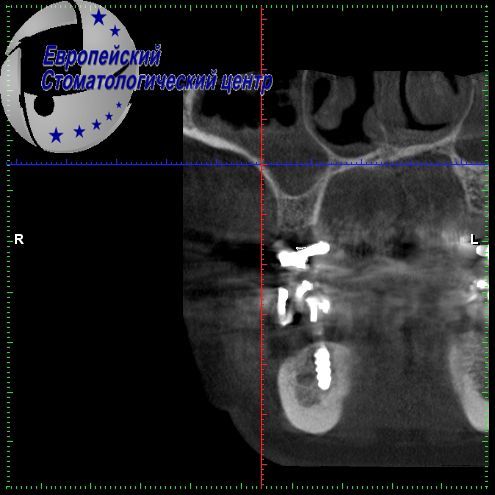

A diagnosis progressing to periodontal disease was established. Due to the insolvency of the remaining teeth, it was decided to remove them. The quality and clinical height of the bone on the upper jaw and the proximity of the mandibular nerve on the lower jaw (see pic. 3_1-3_2) made this case very difficult. However, it was decided to use a minimally invasive implantation method, to do without directional bone regeneration, sinus lifting and augmentation. Basal implants on the upper and lower jaws were applied, they were installed on the day of tooth extraction (see pic. 04).

Picture 3_2

On the lower jaw, implants were circumvented by the mandibular nerve (see pic. 06_1-06_2). On the third day after surgery, temporary non-removable structures were installed (see pic. 05, 07), and after 4 months the temporary constructions were replaced with permanent ones made of PEEK polymer (see pic. 08-09).

Picture 6_1

Picture 6_2